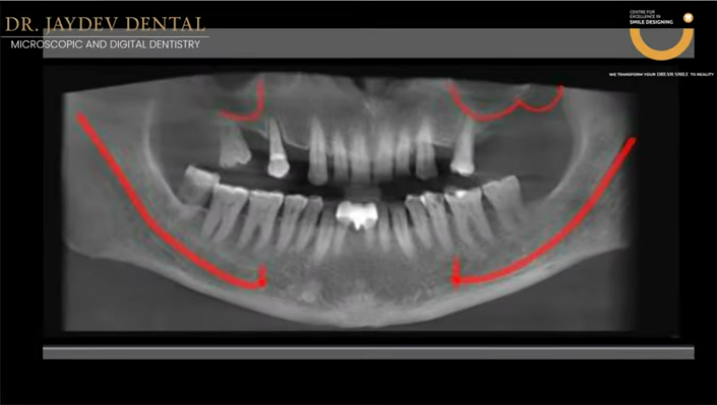

To begin the process, we performed 3D digital scans and CBCT imaging to assess his dental condition, focusing on the upper back teeth and bite alignment. After reviewing the results, we presented multiple treatment options for Mr. Smith’s posterior bite.The initial plan included two implants for the back region, with an additional implant at the backmost region using a sinus lift procedure. However, after discussing his concerns, the patient was strongly opposed to the sinus lift. To accommodate his preferences, we recommended an innovative approach—pterygoid implants, which would allow us to place the implants without the need for the sinus lift.

Phase 2: Implant Placement and Digital Planning

We took 3D digital scans and created a digital guide for pterygoid implant placement. This approach ensured precision in the placement of the implants, minimizing any risks and improving overall success rates. The guided implant placement allowed for optimal positioning, ensuring that the implants were placed in the correct angles for maximum stability and function.The surgical procedure was carried out by our experienced team, including an implantologist, prosthodontist, and critical care specialist. During the procedure, six implants were placed in total—two implants in the front region and one pterygoid implant at the backmost region. The surgery was completed successfully, and the patient was provided with temporary dentures to wear while healing.